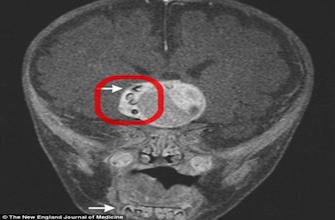

Lorsque les parents et les médecins de ce petit garçon à peine âgé de 4 mois s’inquiètent au départ de son état médical, c’est à cause d’une croissance rapide et atypique du volume de sa tête. Après plusieurs examens, et notamment un scanner de son cerveau, les médecins découvre avec stupeur non seulement, une tumeur cérébrale, mais également la présence au sein de celle-ci, de plusieurs structures ressemblant étrangement à des dents, celles que l’on trouve habituellement au niveau de la mâchoire inférieure.

Immédiatement les médecins décident d’opérer l’enfant pour retirer et analyser cette tumeur inédite. Il subit donc avec succès une opération du cerveau avec exérèse de la tumeur et au cours de laquelle les médecins confirment que celle-ci contient bien plusieurs dents entièrement formées. Après analyse du tissu tumoral, ces médecins ont finalement déterminé que le bébé souffrait d’un craniopharyngiome, une tumeur cérébrale rare qui peut se développer jusqu’à atteindre la taille d’une balle de golf, sans se propager à d’autres organes toutefois. « Les chercheurs ont toujours soupçonné que ces tumeurs puissent se former à partir des mêmes cellules que celles impliquées dans la fabrication de dents, mais jusqu'à présent, aucun médecin n'avait jamais vu de véritables dents au sein de ces tumeurs, a déclaré le Dr Narlin Beaty, l’un des chirurgiens qui a opéré cet enfant au centre médical du Maryland. Les craniopharyngiomes contiennent souvent des dépôts de calcium, mais dans leur article publié dans le NEJM, les auteurs expliquent leur stupeur lorsqu’ils ont découvert de vraies dents.